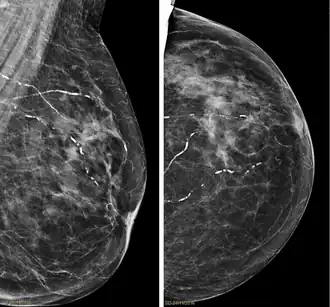

![]() Mamografías de la mama derecha en que se ven varias arteriolas calcificadas. Paciente de 94 años. | ||